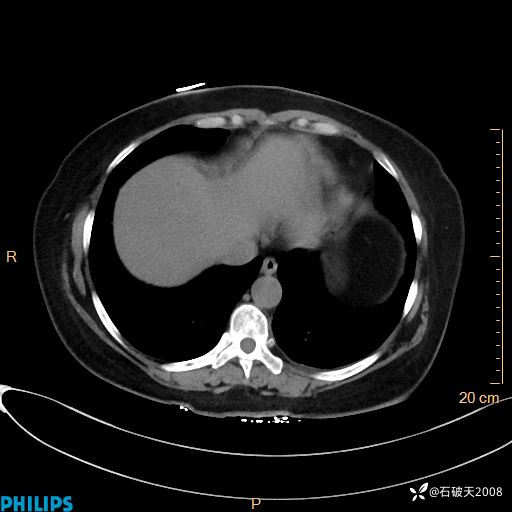

肺结节病?纵膈型肺癌?淋巴瘤?有点意思,欢迎围观

女 52岁 主 诉:咳嗽10余天,咳痰2天。

现病史:10余天前无明显诱因出现咳嗽,呈阵发性干咳,伴咽喉部发痒,无咽痛,无咳痰,无鼻塞、流涕、打喷嚏,无发热、畏寒、寒颤,无头痛、头晕,无胸闷、胸痛,无反酸、烧心,无腹痛、腹泻,无尿频、尿急,无皮疹等,在当地诊所求治,给予口服药物治疗(具体不详),病情无好转。遂在当地社区卫生服务中心开具口服药物治疗(具体不详),疗效欠佳。2天前出现咳痰,在我院门诊求治,行胸部CT提示肺部感染,建议住院,患者要求口服药物治疗,目前仍咳嗽、咳白色粘痰,白天量多,夜间自觉喉部喘鸣音,遂再次来院就诊,以“肺部感染”为诊断收入院。发病以来,神志清,精神可,饮食可,夜间睡眠差,大小便正常,近期体重无明显变化。

动脉期